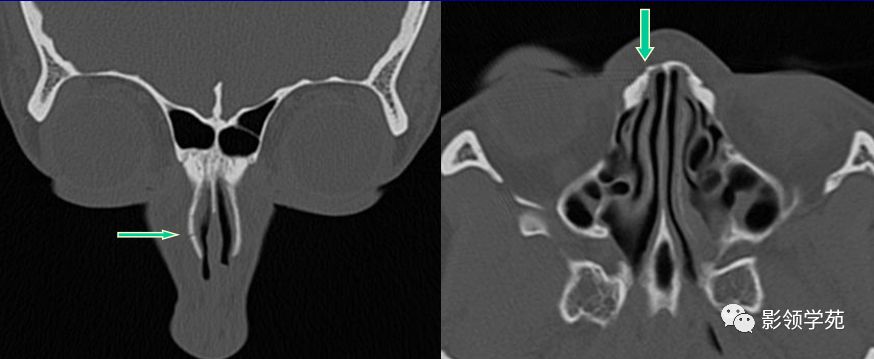

线性骨折 粉碎骨折

右侧鼻骨线形骨折

鼻骨线形骨折

左侧鼻骨线形骨折